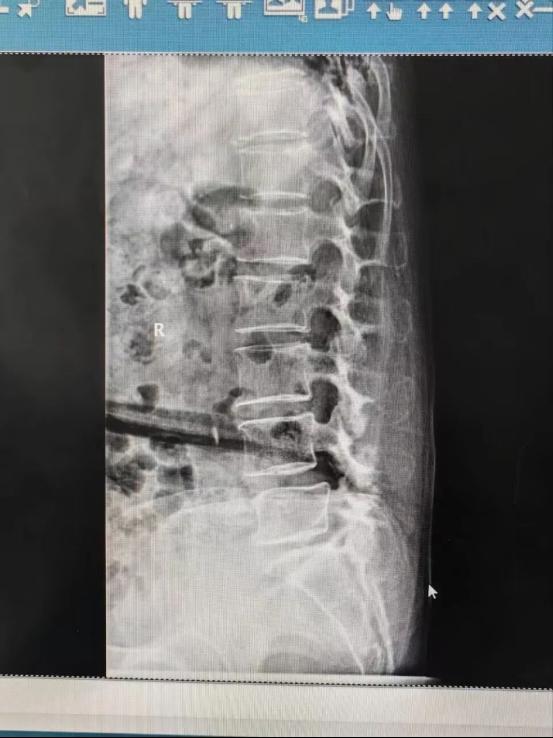

术前X线显示:腰4-5一度滑脱